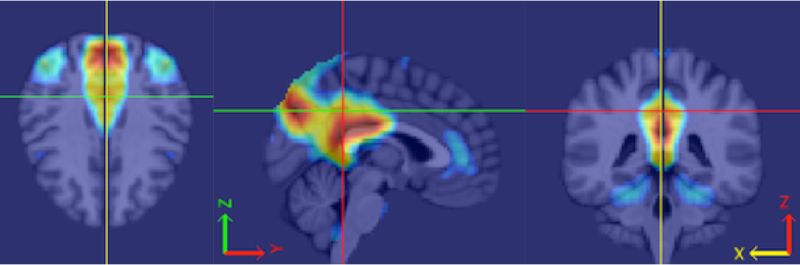

Caffo’s specialty is a kind of brain scan called “functional magnetic resonance imaging” — or fMRI for short. Unlike X-rays, which show only the brain’s structure, the colorful pictures created using fMRI show the brain at work. Neuroscientists are especially interested in seeing which parts of the brain light up (and which don’t) when someone does a particular task. This helps them map connections between different parts of the brain.

Caffo works at the Bloomberg School of Public Health at Johns Hopkins University in Baltimore. There, he separates real brain signals contained in fMRI images from meaningless static. Statistics provides the tools he needs to erase that confusing “noise.”

Using fMRI images for prediction poses a challenge, however. Usually, scientific theories relate one quantity (which we’ll call x) to another quantity (which we’ll call y). For example, how fast a person throws a ball (x)determines how far it will go (y). But what can be done when the values for x or y are not numbers, but pictures?

So far, the best solution has been to turn pictures into numbers. Doing that creates a lot of numbers. Think of the old saying: A picture is worth a thousand words. But with a single fMRI scan, a picture may translate into hundreds of thousands of numbers. Statisticians need fancy math to compress and process these data in ways that give scientists something meaningful.